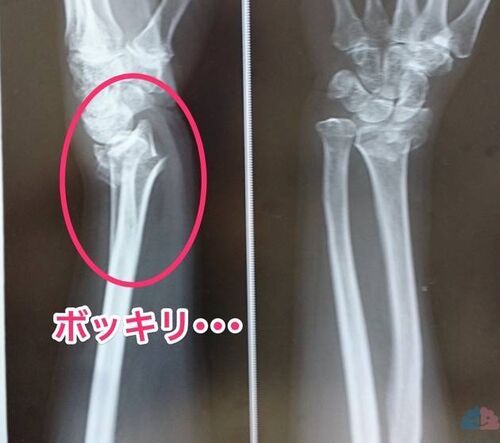

つい先日、母が転倒して手を骨折してしまった。 主介護者に起きたイベントによって今後の介護方針に新展開があったので、そのご報告。何かの参考になれば幸い。